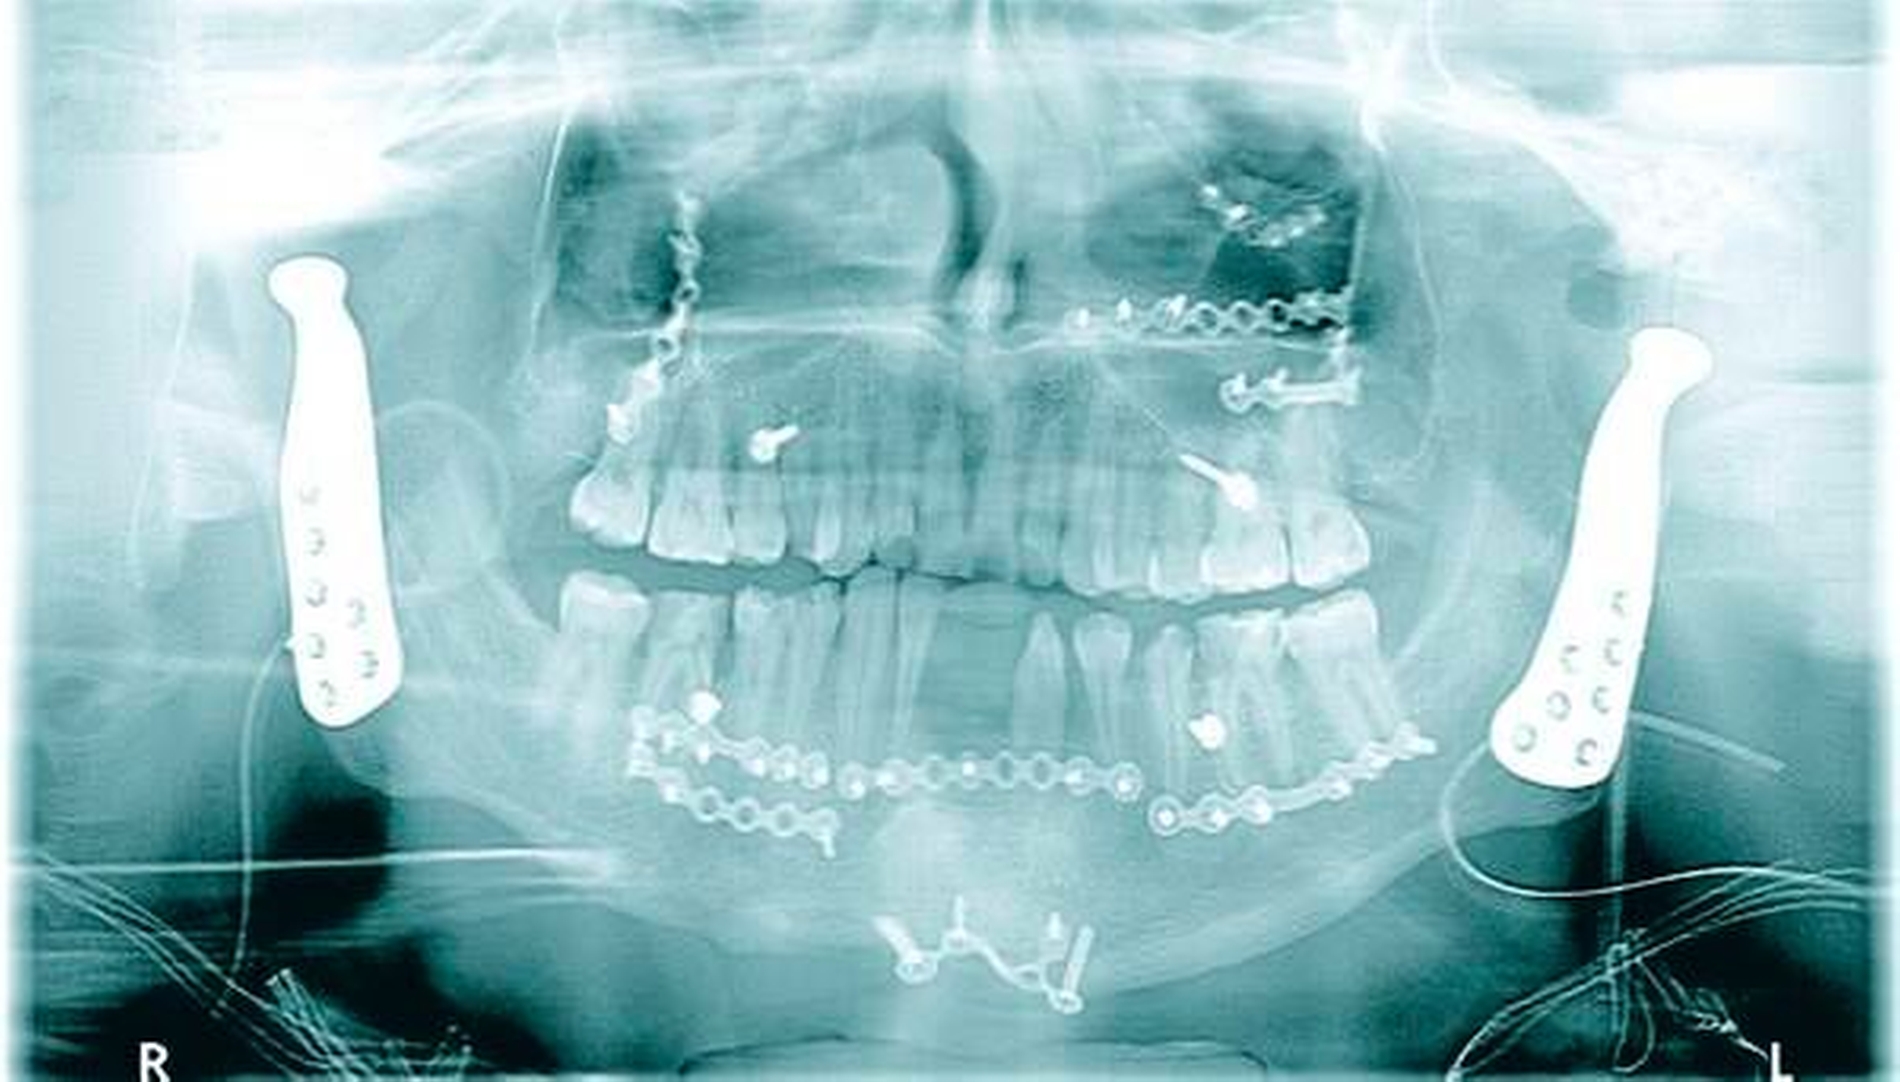

Vor der definitiven Fixierung der Prothesen wurden Dummys als Test eingesetzt, um eine optimale Positionierung der passgenauen finalen Prothesen zu erreichen (Abbildung 2 bis 9). Abbildung 10a und 10b zeigen die postoperative Röntgenkontrolle.

Am zweiten postoperativen Tag begann eine intensive Physiotherapie. Bereits fünf Wochen später betrug die maximale Mundöffnung aktiv 26 mm (Abbildung 11), passiv 32 mm. Nach der Stabilisierung einer individuell maximalen Mundöffnung ist die dentale Sanierung geplant, an die bislang situationsbedingt in keiner Weise zu denken war.